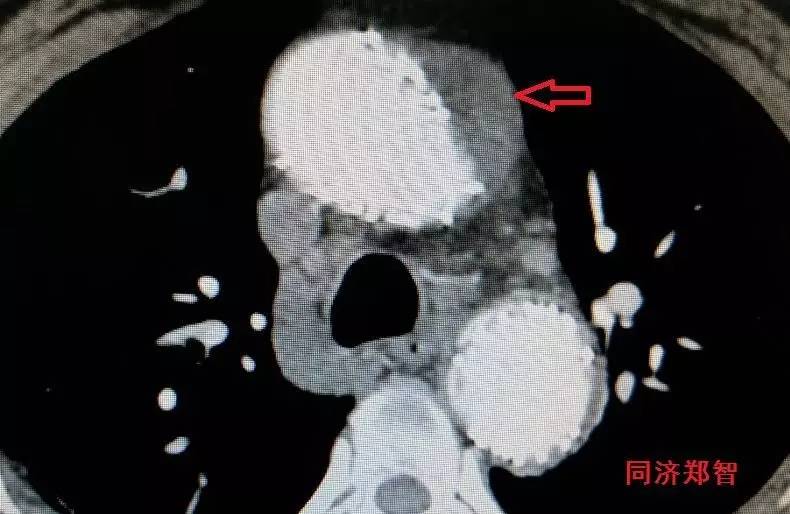

CTA显示升主动脉穿透性溃疡合并壁间血肿(图13)。

图13